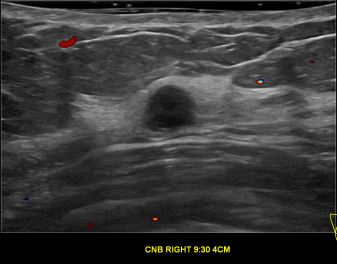

상기환자는 70대초반 여성분으로 추적관찰 초음파상 의심스러운 우측혹 조직검사 시행해 유방암으로 진단되었습니다